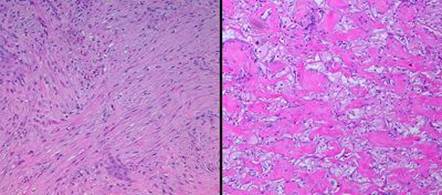

Figure 11   (top)

(a, left)  Fibroplasia in a normal wound.  This is the zone of  fibrous consolidation.  Densely packed fibroblasts are making thick chords of collagenized scar.  As the process evolves, increasing connective proteins will make the scar progressively less compliant or distensible.  These fibrous chords are multidirectional at their inception, but subjected to tensile loads, they will reorient themselves to resist that load, distorting features and obstructing motion.

(b, right)  Integra collagenization.  Cellularity is low.  Collagen conforms to the matrix, forming discrete packets molded within the pores of the sponge.  Spaces and interruptions, incoherence, between collagen clusters mean that the material remains more fluid and deformable, more like normal tissue, less like scar.

(a, top left)  Normal reticular dermis.  Large, parallel, mostly transverse collagen bundles are separated by interstitial spaces.  Typical fibroblasts in typical densities are dispersed throughout

(b, top right)  Normal reticular dermis from another subject.  There is variability in the size and orientation of dermal collagen from specimen to specimen, due to location, skin thickness, local biomechanics, orientation of the specimen cuts relative to local skin anisotropies (Langer’s lines, fibers seen parallel or on end), and intersubject variability.  Thus the two top specimens look different, but both are normal reticular dermis.  Collagen bundles are large, somewhat coiled, wavy, or springy.  They are largely individualized and distinct, separated by interstitial spaces.  These factors permit elastic compliance of the material, and normal motion of related body parts

(c, middle left)  Young scar.  This is normal repair at peak fibroplasia.  The scar is highly cellular, and in ensuing weeks it will become heavily collagenized.  Dense packing of fibers means no fluidity of the material.  Lack of folding or waviness means that there can be no distensibility.  This is the stuff that causes contractures, strictures, stenoses, stiffness, and other typical adverse effects of scar.

(d, middle right)  Young Integra.  In comparison, young Integra has a completely different histology, morphology, and biomechanics.  The matrix itself partitions the collagen, having a similar effect on the structure and mechanics of the material that the interstitial spaces have in normal dermis.  While it does not look precisely like normal dermis, it has many of the same structural properties, and it can be expected to behave like normal dermis.

(e, bottom left)  Matured scar.  This scar, at 2 years old, is still cellular compared to normal dermis, but not by much.  The scar collagen has undergone a gradual transformation.  It is now bundled and springy, looking mostly like normal dermis.

(f, bottom right)  Old Integra at 4 years.  The original matrix is largely gone in this area (but it is still abundant in some other out-of-view areas of this biopsy).  For septae that do remain, their morphology is still unaltered.  Just as with scar, normal physiological collagen remodeling is also slowly making this specimen look like normal dermis.  However, in sharp contrast to scar, Integra has, from the outset, a structure and properties that are already very close to dermis, thereby avoiding scar complications.